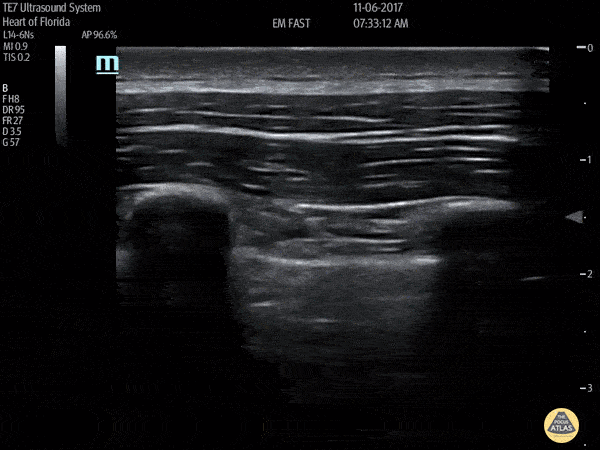

Pulmonary - No Lung Sliding

This image demonstrates lack of lung sliding which is a finding that can be seen in a pneumothorax. Francisco Norman